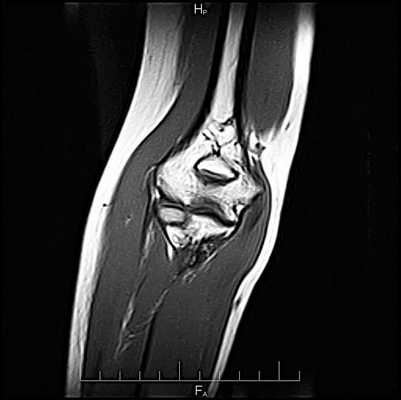

МРТ в FABS-положении локтевого сустава в норме